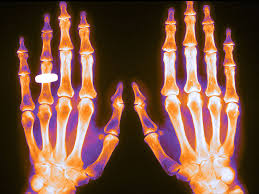

Osteoporosis parte 2: Tratamiento farmacológico

Esta es la segunda entrega de la Folia DOC  dedicada a osteoporosis. La primera se enfocó en el diagnóstico, prevención y medidas no farmacológicas, y en esta se aborda el tratamiento farmacológico. El mismo variará según el riesgo estimado de fractura, la consideración de la eficacia y seguridad de los diferentes fármacos, la conveniencia de su administración y las preferencias de las pacientes. FoliaDOC, Fundación FEMEBA, 27 de enero de 2025.